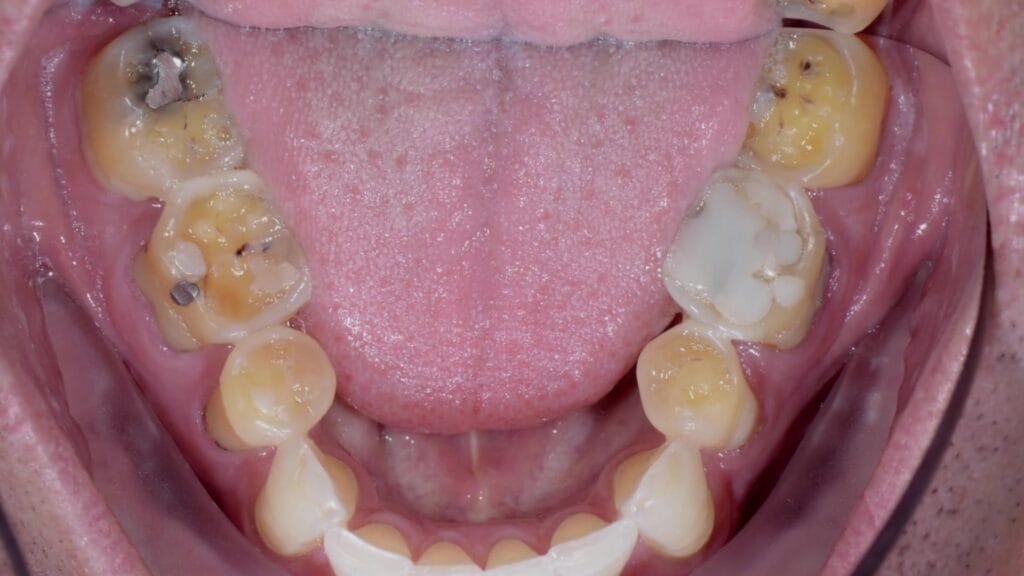

What can it mean when posterior wear is greater than anterior wear?

Dr. Laura Wittenauer discusses what is the root cause when posterior wear is greater than anterior wear.